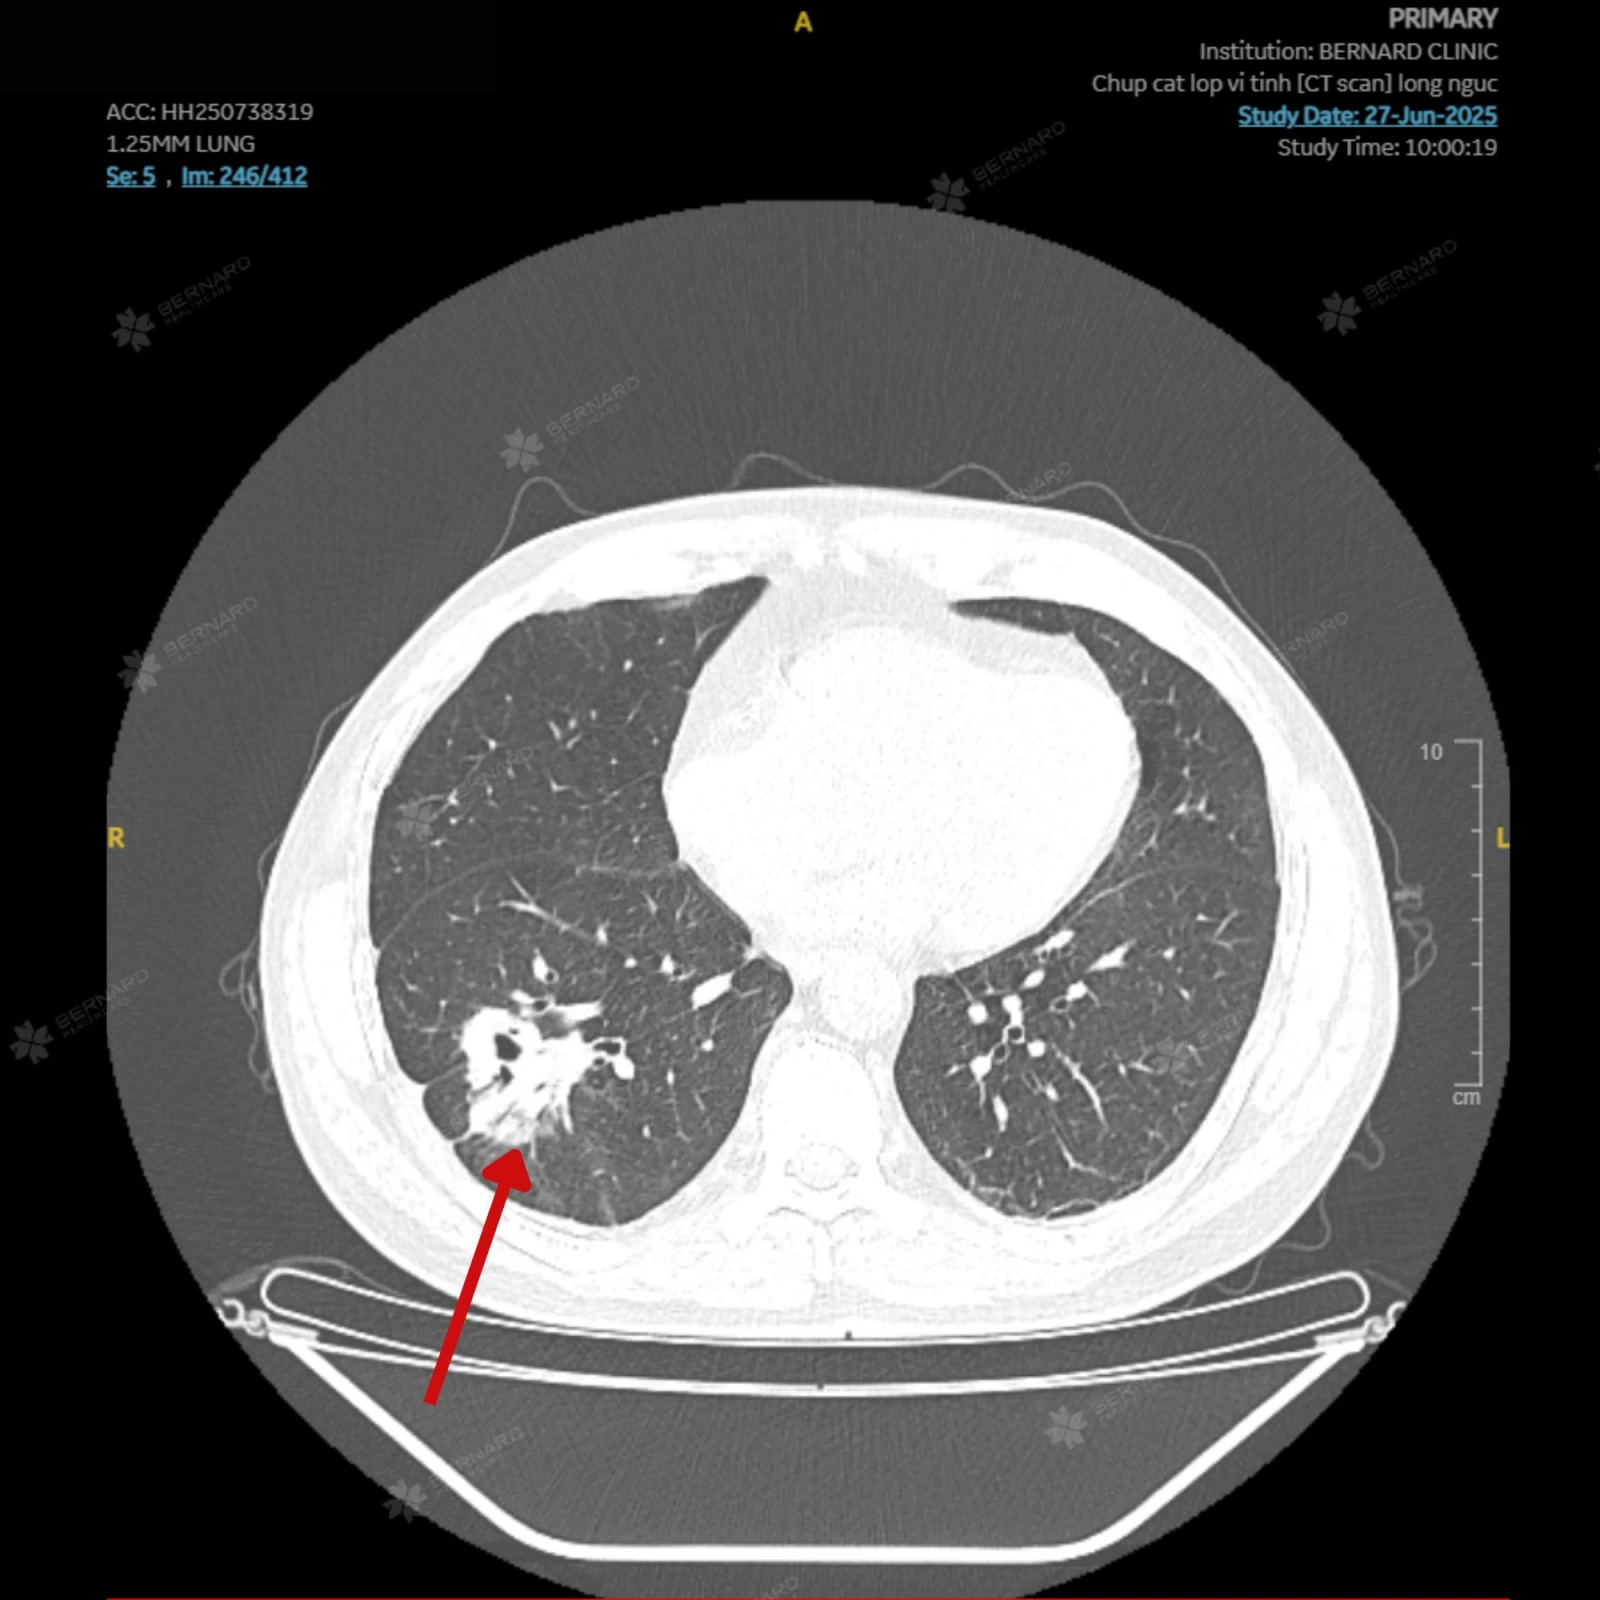

Kết quả CT Scan lồng ngực ghi nhận: Tổn thương choán chỗ lớn thùy dưới phổi phải, kích thước khoảng 3.8 x 4.0cm, đậm độ trung bình, không đồng nhất, kèm đông đặc, bờ tủa gai co kéo xung quanh, bắt thuốc không đồng nhất.

Các đặc điểm hình ảnh học này gợi ý tổn thương u phổi, bệnh nhân được chỉ định theo dõi sát nguy cơ ung thư thùy dưới phổi phải và tiếp tục làm rõ bản chất tổn thương theo phác đồ chuyên môn.